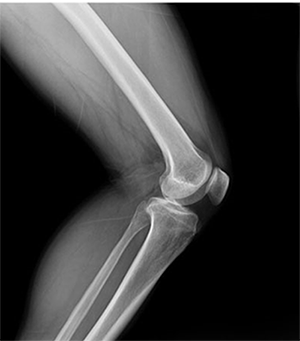

PLD6500系列是普利德研發(fā)的醫(yī)用數(shù)字X線攝影機,采用雙立柱結構,可供各級醫(yī)院放射科對頭部、胸部、腹部、腰椎、四肢等部位進行立位、臥位、正位、側位的數(shù)字攝影檢查。

便于對關節(jié)等復雜部位的多角度攝影檢查。